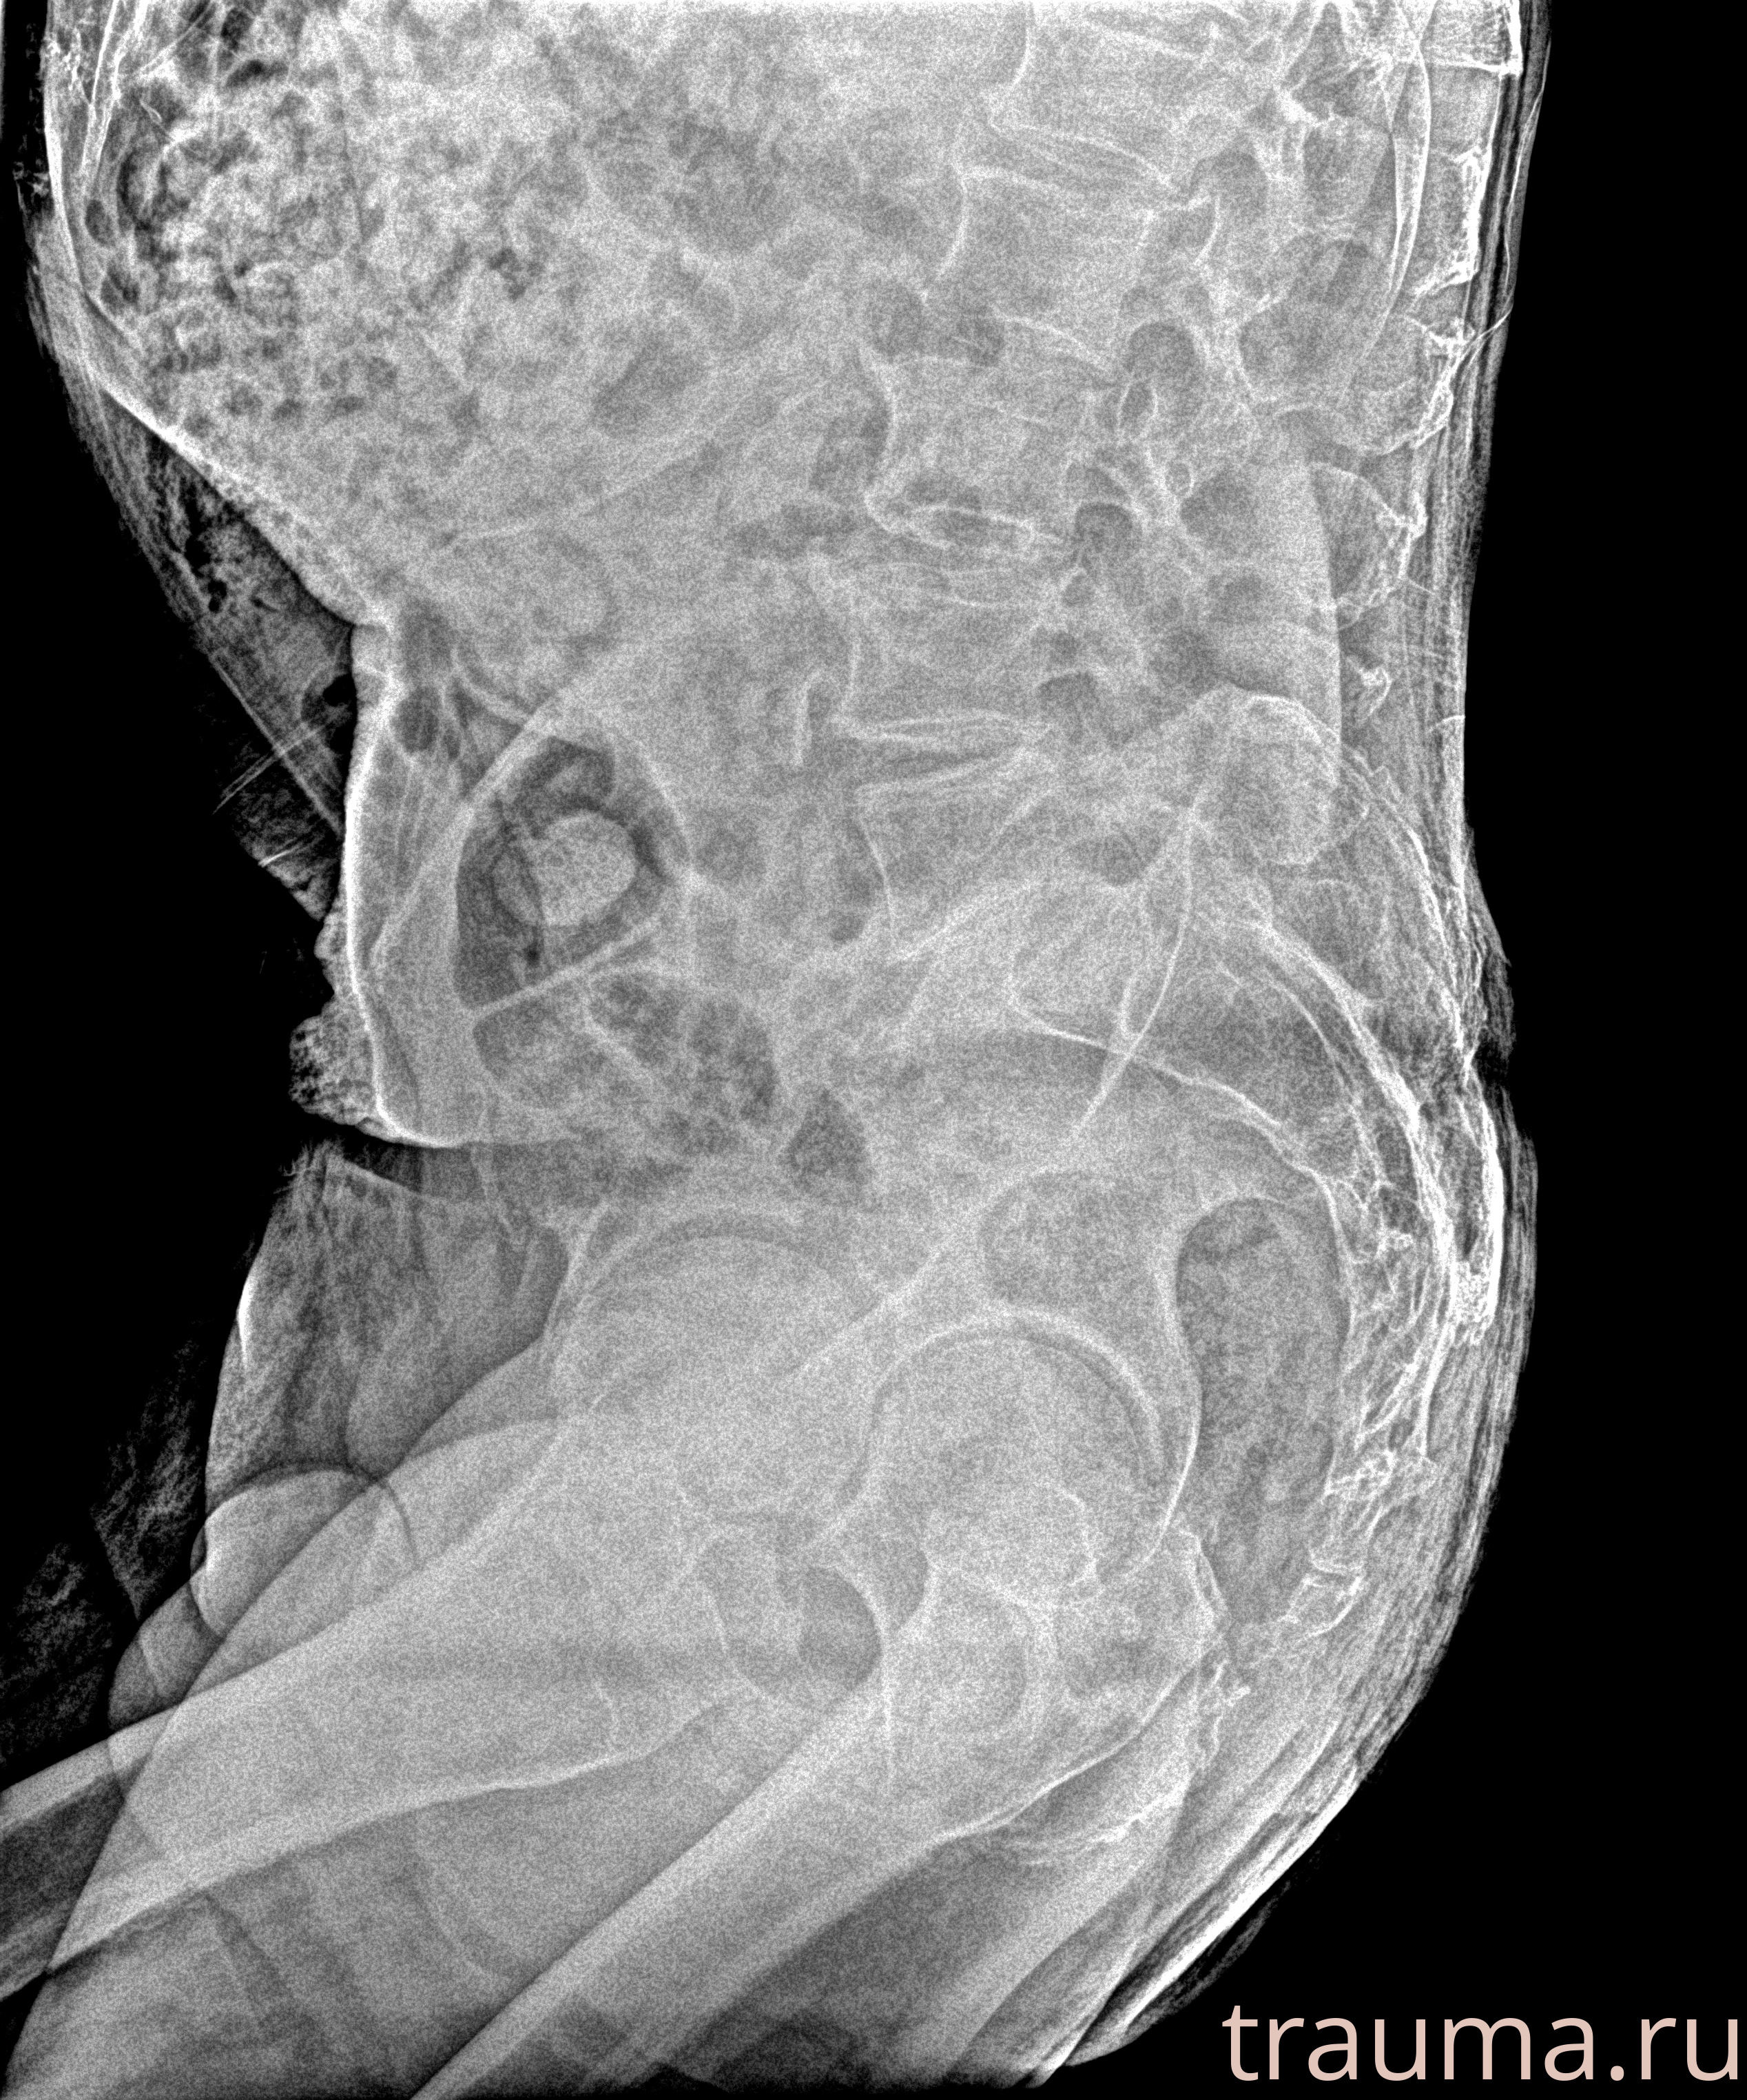

Рентген на дому: по вашему адресу приезжает врач-рентгенолог, травматолог-ортопед с мобильным рентгеновским аппаратом, проводит диагностику травмы или заболевания, делает необходимые рентгенограммы, дает рекомендации по дальнейшему лечению. Получить качественные снимки в домашних условиях возможно благодаря уникальной методике, разработанной МосРентген Центром для института  Склифосовского